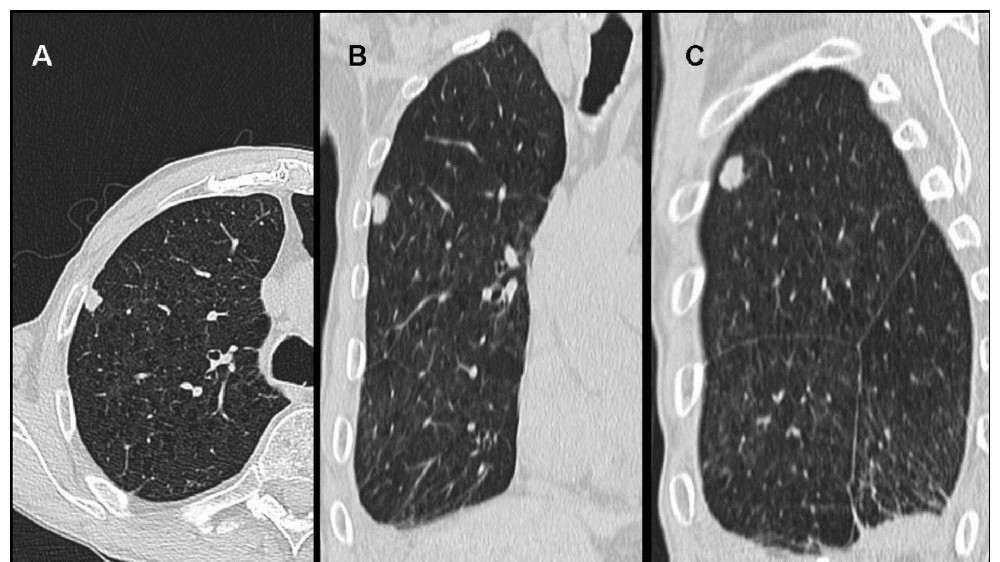

透過對間皮瘤 (惡性間皮瘤) 的進階瞭解、改良的診斷影像以及新陳代謝的弱點,我們的目標是優化病患的療效,在 2025 年前將惡性間皮瘤的治療過渡到all cancers所預想的慢性、可管理的照護。